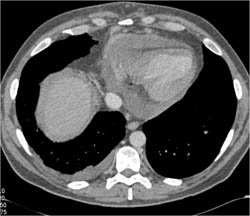

Ascending Aortic Aneurysm Repair With Composite Graft